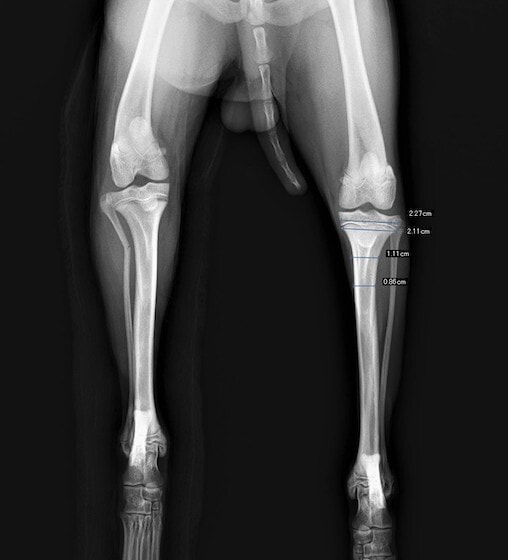

症例3:キルシュナーワイヤーのピンニングによる整復

ペルシャ猫 11ヶ月齢 雄

他院にて左大腿骨遠位の成長板骨折(salter-harrisⅠ型)が認められており、治療相談を目的として来院。当院にて、キルシュナーワイヤーを用いたピンニングにより骨折部位の整復を行いました。術後の経過は良好で、現在も経過観察中です。

術前レントゲン

術後レントゲン

機器

Arthrex社のターゲティングデバイスを用いてピンニングの位置を調整することで、確実な固定を行っています。当院ではこの手術器具以外にも、人の手術にも使用される様々な器具を導入し、手術精度を高め、また医療メーカーと新しい器具の開発、試作にも取り組んでおります。